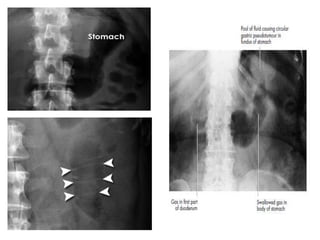

• #14 In the supine position, depending on how much is present, the gas in the stomach will rise anteriorly to outline variable volumes of the body and antrum of this structure, to the left of and across the spine around the lowermost thoracic or upper lumbar levels. Simultaneously the resting gastric fluid will form a pool in the fundus beneath the diaphragm, posteriorly on the left-hand side, creating a circular outline – the ‘gastric pseudotumour’ – which should not be mistaken for an abnormal renal, adrenal or splenic mass, although occasionally it is and requests are received in X-ray to ‘investigate the left upper quadrant mass’. Try to avoid this mistake. The mass can be made to disappear by turning the patient prone or sitting him upright, when the familiar fundal gas bubble, commonly best seen on chest X-rays, will appear with a fluid level directly beneath the medial aspect of the left hemidiaphragm

• Stomach

• The stomach may be visible if it contains gas/air. It is not visible if it

is either completely empty, or fluid filled.

• Small bowel (duodenum to terminal ileum)

• Generally the small bowel lies centrally within the abdomen. The

valvulae conniventes (also called plicae circulares) are thin, circular,